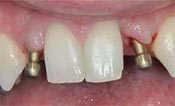

安卓健临床案例分享

安卓健种植产品销往全球100多个国家精密工程CFDA

权威认证,可放心使用。安卓健种植体手术程序简单,

更少创伤,更快恢复,更加安心。